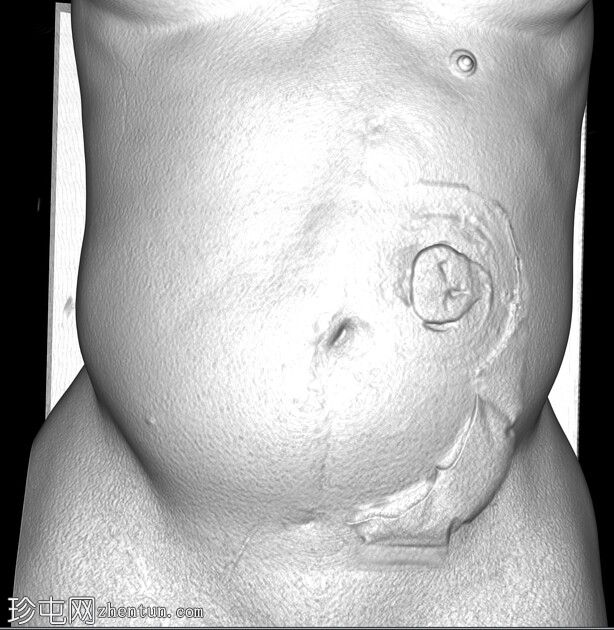

SSD

正位片

PACS系统回顾既往腹部和盆腔CT的代表性图像证实了结肠造口和左侧腹部造口的存在,这解释了腹部X线片上发现的假瘤样改变。在三维皮肤表面图像上也可以看到结肠造口袋的轮廓,这解释了腹部X光片上出现的非解剖性透亮区。